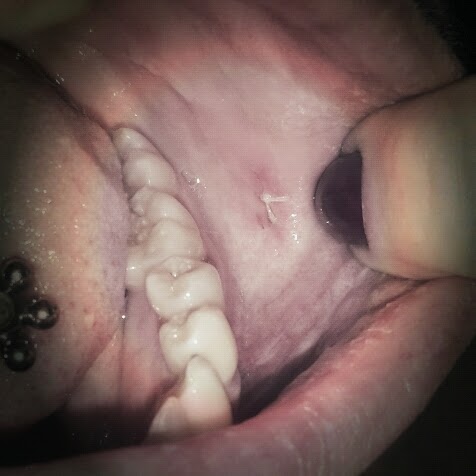

Jag har en bild på hur det såg ut dagen efter, mest för att du som kanske ska göra det här ska se hur ofarligt det är och hur fint det ser ut efteråt. Men jag placerade fotot medvetet längst ner för att känsliga magar ska slippa vända sig.

Så här litet och snyggt blev såret i munnen!

Hon satte ett stygn över hålet men det var mer för att jag skulle slippa blodsmaken sa hon, annars läker det relativt fort i kinden. Däremot så sa hon att det kunde göra lite ont när bedövningen släppt efter 2-3 timmar och det måste jag ju säga att det kändes lite, men inte farligt alls. Vant såg hon dessutom till att hålet hamnade lagom långt in och lagom långt ner för att jag inte skulle kunna bita mig där så länge jag var bedövad och inte heller störas av det under läkningen.

När bedövningen hade verkat så kändes absolut ingenting. Jag bad henne att berätta vad hon gjorde hela tiden, för jag tycker inte om att inte veta och riskera överraskningar. Så när hon stansade ut biten från kinden så hade jag inte märkt att hon gjorde det om hon inte hade sagt något. Fick se den lilla rackaren efteråt och den var ändå så pass stor att jag tackade övre makter efteråt för bedövningen.